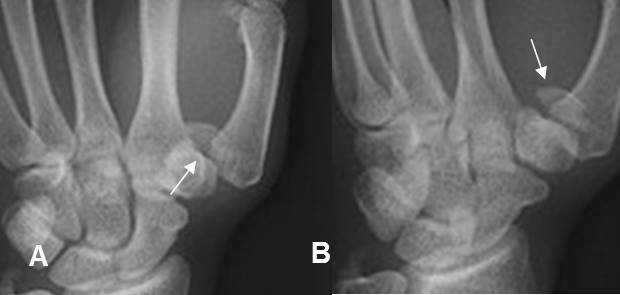

A: Rx AP y B: Rx oblicua. Luxación de articulación carpometacarpiana del pulgar, sin fractura del metacarpiano. Irregularidad en el trapecio, que puede corresponder a fisura.

Fig 175 B. Luxofractura de Bennet.

A: Rx AP y B: Rx oblicua. Subluxación de la articulación carpometacarpiana del pulgar y fractura en la base del metacarpiano, por luxofractura de Bennet.